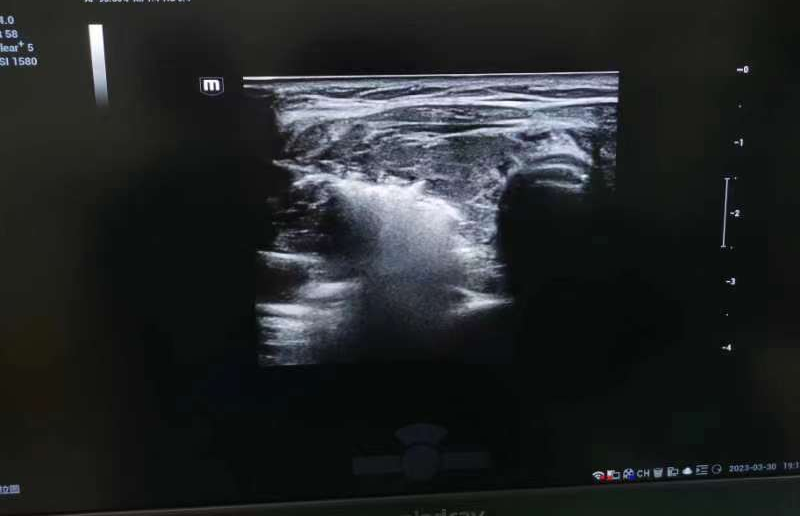

图片 3.png

彩超图像

通过使用直径1.6mm的微波消融针,在彩超介导下经颈部穿刺进行甲状腺组织消融,对颈部皮肤创伤仅有针眼大小,对比消融前后有肉眼可见的效果。